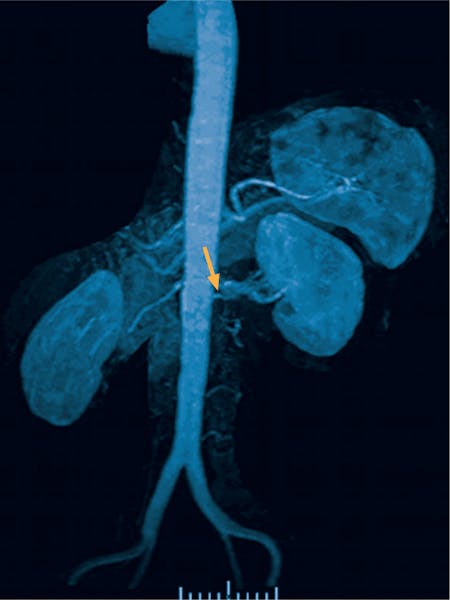

Diagnosticul stenozei de arteră renală poate fi pus în urma diferitelor teste de specialitate, cum ar fi ecografia Duplex, angiografia, angio-CT, angio-RMN.

Angio-CT este combinația dintre angiografie și computer tomograf, ce permite obținerea de imagini tridimensionale, cu ajutorul substanței de contrast.

Angio-RMN este modalitatea prin care se pot obține imagini detaliate cu ajutorul substanței de contrast introdusă prin venele de la nivelul antebrațului.